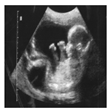

| PEI | ![]() | ![]() | ![]() | ![]() | ![]() | ![]() | ![]() |